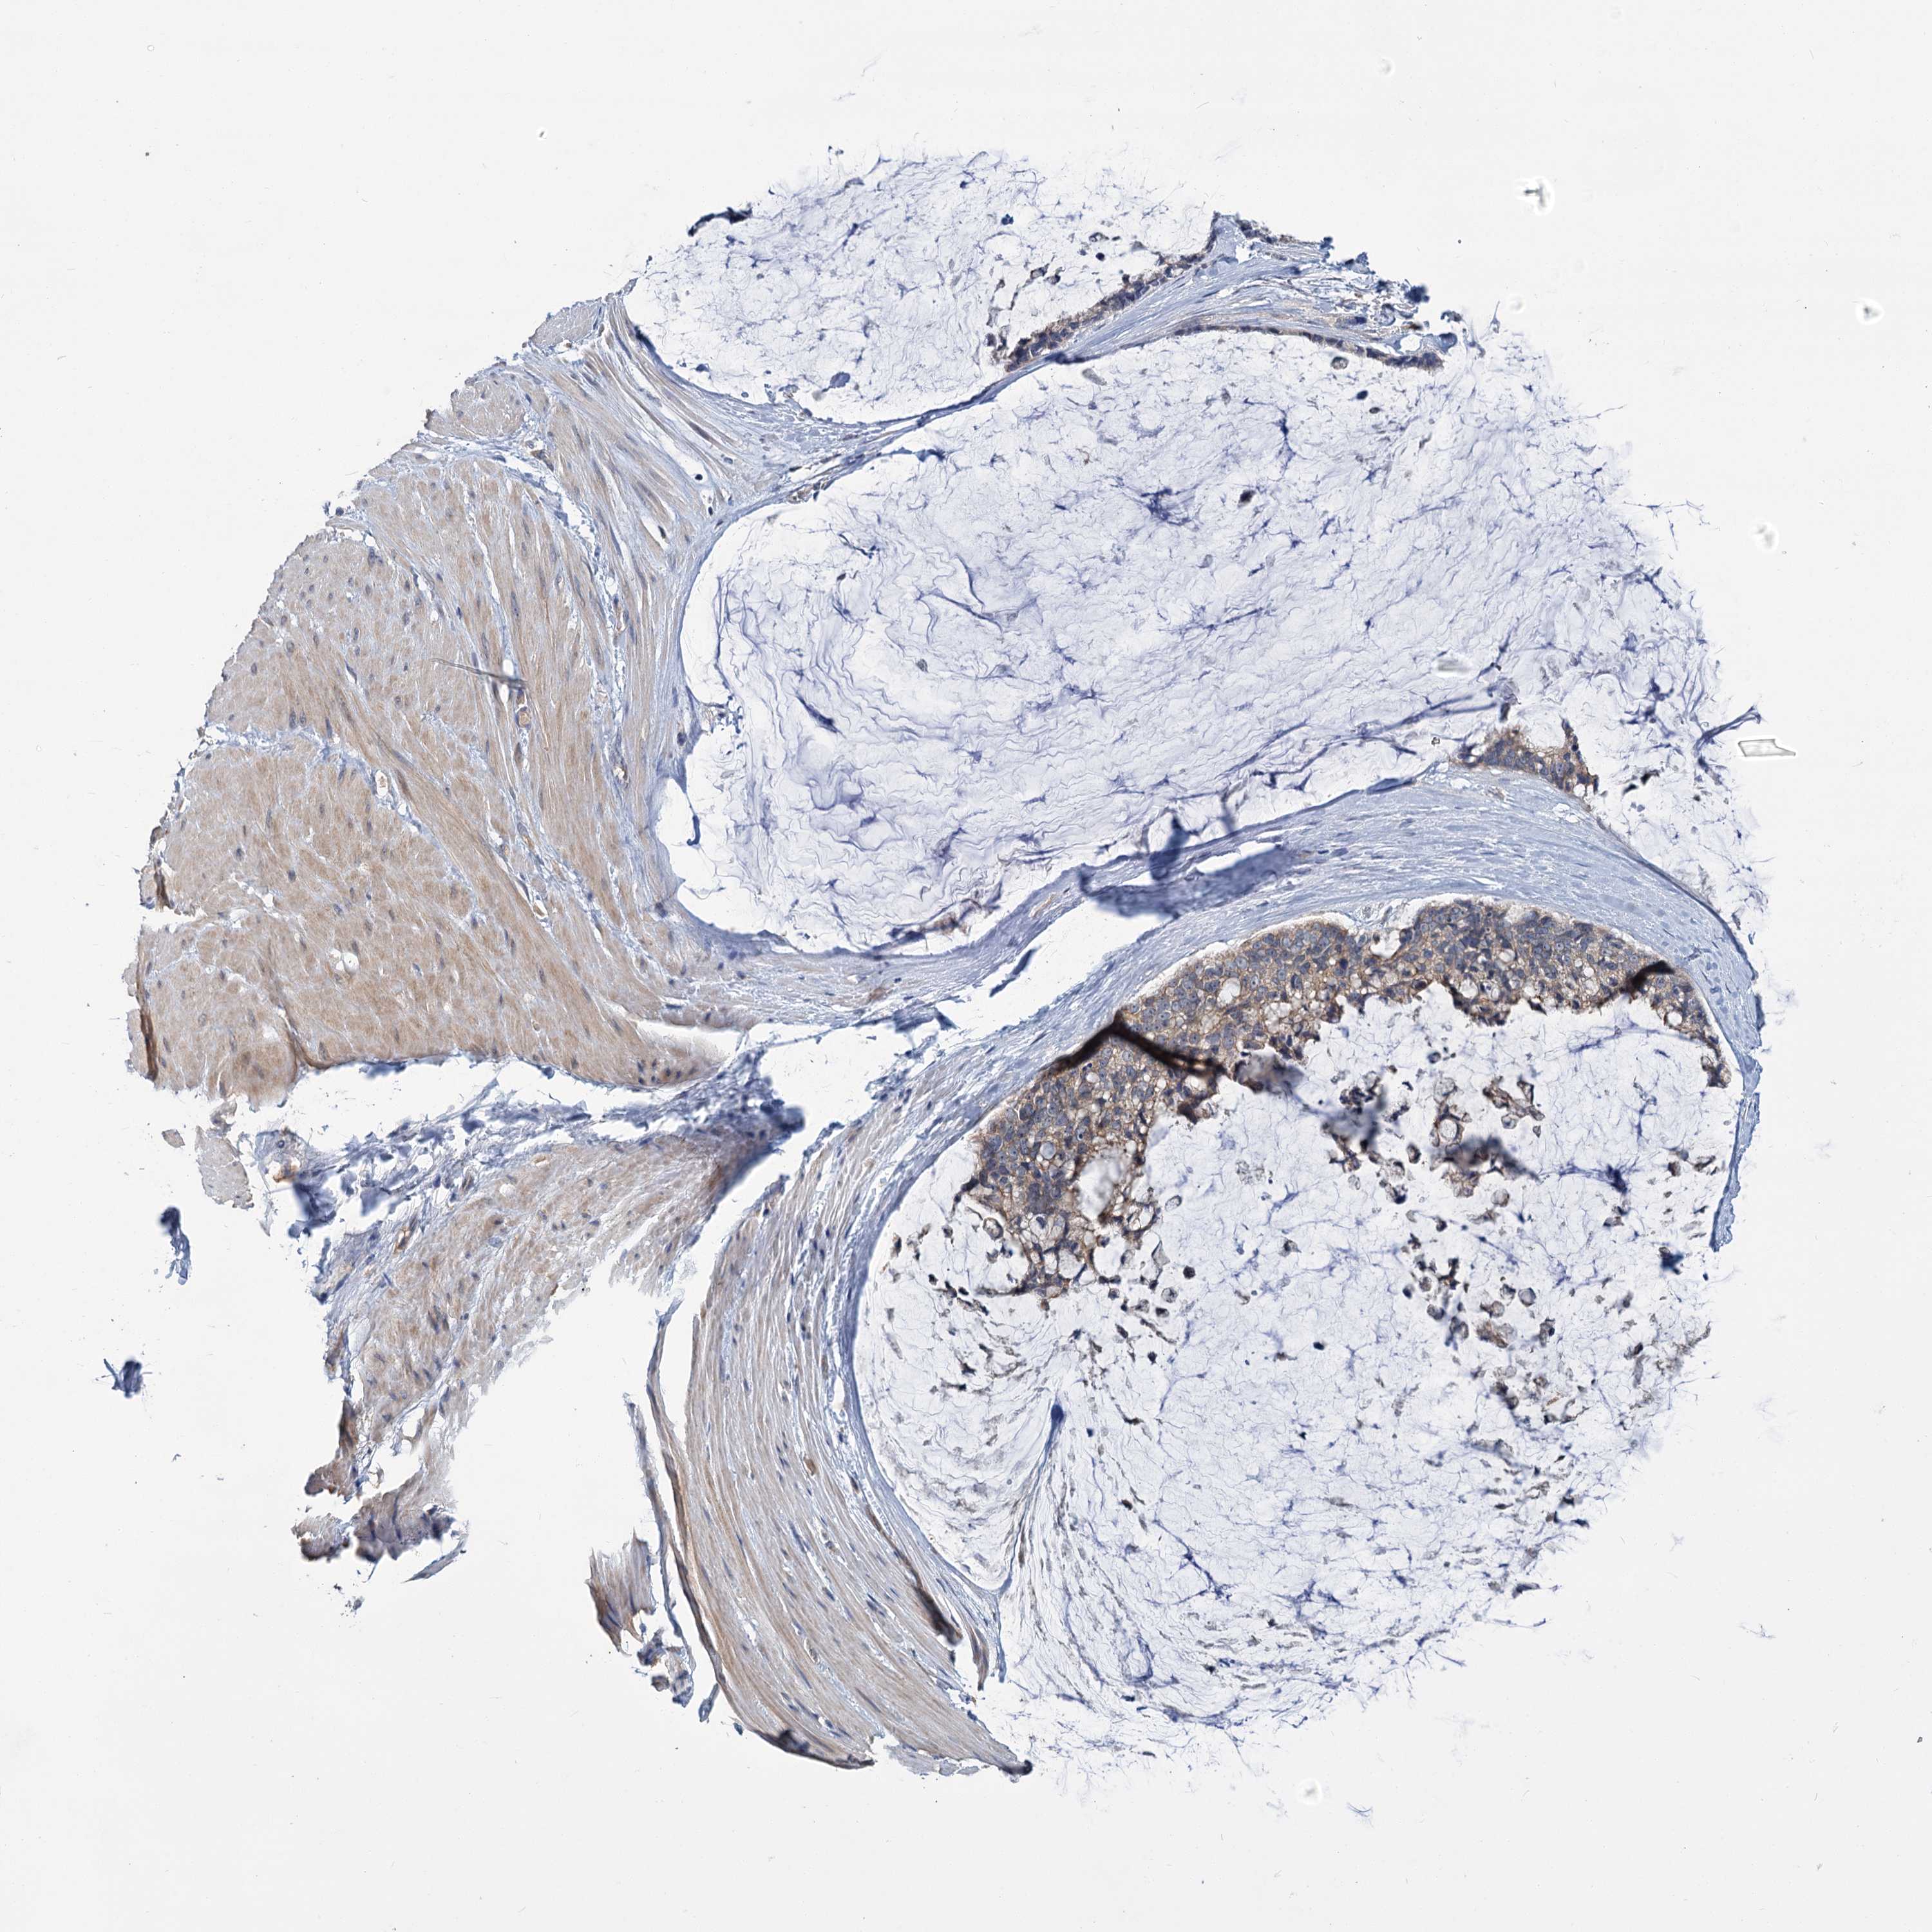

OVARIAN CANCER - Protein expressioni

A mouse-over function shows sample information and annotation data. Click on an image to view it in a full screen mode. Samples can be filtered based on level of antibody staining by selecting one or several of the following categories: high, medium, low and not detected. The assay and annotation is described here.

Note that samples used for immunohistochemistry by the Human Protein Atlas do not correspond to samples in the TCGA dataset.

Antibody stainingi

Antibody staining in the annotated cell types in the current human tissue is reported as not detected, low, medium, or high, based on conventional immunohistochemistry profiling in selected tissues. This score is based on the combination of the staining intensity and fraction of stained cells.

Each image is clickable and will lead to virtual microscopy that enables deeper exploration of all samples and also displays staining intensity scores, fraction scores and subcellular localization as well as patient and tissue information for each sample.

Antibody HPA039015

Antibody HPA039016

Cystadenocarcinoma, mucinous, NOS